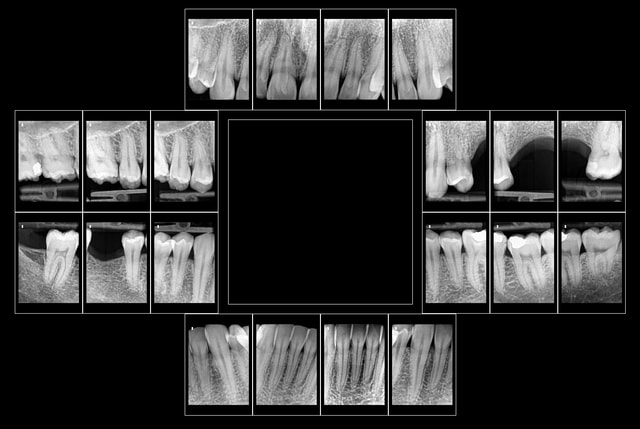

Bon je m'y colle, c'est pas le même niveau qu'olivier, mais ce sujet étant censé être pour les débutants je poste.

Patient 26 ans, à qui il manque 46, 25 et 26.

Pour l'instant je vous propose la partie préparation et mise en place de l'implant en 46, la suite peut être bientôt.

Dans l'ordre si le site veut bien, wax-up ( cirage pour céramik ;) ) , guide radio, et scan.

Photos pré-op, indicateur de direction en place et post-op.

Il s'agit d'un implant astra osseospeed de 5 mm de diamètre et 9 de long.

Prothèse prévue à 6 semaines.